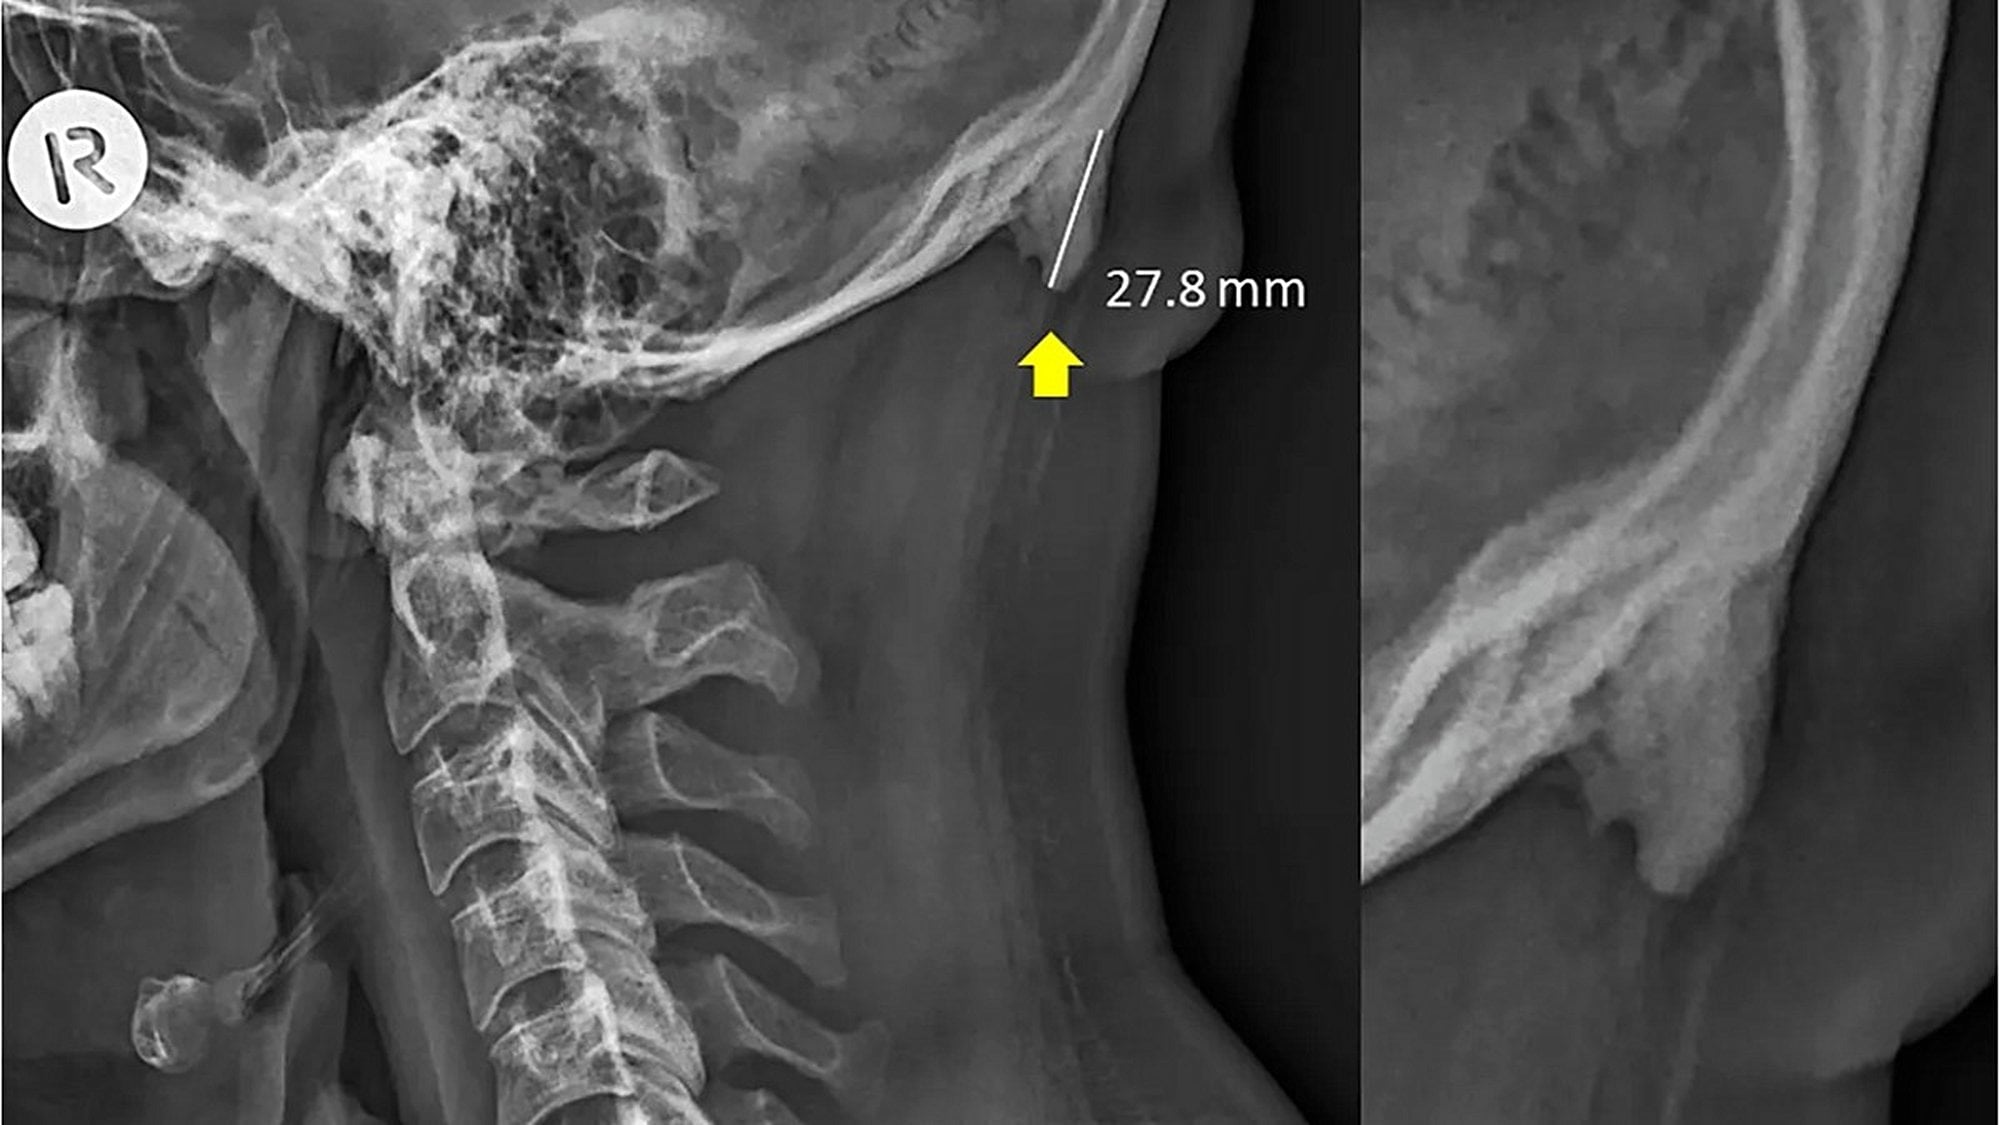

Söz konusu kemik uzantısını ortaya çıkaran veriler, 3 yıldır boyunca Avustralya'nın Queensland bölgesinde çekilen X-ışını taramalarından geliyor. Bu taramalarda, söz konusu çıkıntıların da bulunduğu bölgenin fotoğrafları çekildi. Normalde bu kemik uzantıları çok şaşırtıcı değil ve yaşlılarda görülüyor; çünkü yıllar yılı hayatta kalıp, boyun kaslarına yük bindirince, bu kemikler de ilerleyen yaşlarda gelişebiliyor. Ancak şaşırtıcı olan, genç yetişkinlerde de bu kemiklerin gözükmeye başlamış olması. Hem de kimi zaman bu genç yetişkinlerde yaşlılardan bile daha uzun kemikler görülüyor!

Aynı araştırmacılar, 2016 yılında Journal of Anatomy dergisinde yayınladıkları makalede, 18-30 yaş arası 218 kişiye ait X-ışını taraması fotoğrafını analiz ederek bu kemik büyümesinin genç yetişkinlerin %41'inde görüldüğünü tespit etmişlerdi. Bu kemikler, erkeklerde kadınlara göre daha belirgindi.

Genişlemiş dış oksipital çıkıklık (İng: external occipital protuberance) adı verilen bu durum eskiden gençlerde çok nadiren görülmekteydi. Ancak 2018 yılında Clinical Biomechanics dergisinde yayımlanan bir çalışma, bunun gençlerde daha sık görülmeye başlandığını ve sebebinin genetik veya enflamasyon gibi faktörler olmadığını; daha ziyade mekanik yük binmesi sonucu olduğunu gösterdi.

İşte bundan yola çıkan araştırmacılar, nihayetinde 18-86 yaş arası insanlara ait 1200 X-ışını taramasını inceleyerek, bu kemiklerin popülasyonun %33'ünde bulunduğunu ve şaşırtıcı bir şekilde artık yaş ilerledikçe bu kemiklerin kısaldığını gösterdiler! Bu keşif, yerleşik bilimsel bilgilerimizle fazlasıyla zıt. Çünkü normalde bu çıkıntılı kemiklerin ilerleyen yaşlarda daha da uzadığı düşünülmekteydi! Shahar şöyle diyor: